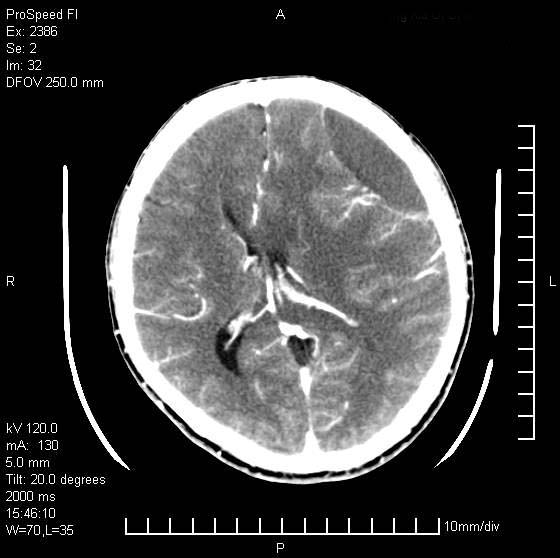

以下是引用天南地北在2007-9-19 18:43:00的发言:[br]典型慢性硬膜外血肿[br][br][本贴已被 天南地北 于 2007-9-19 18:44:11 修改过]

以下是引用曼一拍在2007-9-20 11:06:00的发言:[br]支持慢性硬膜下血肿.[br]慢性硬膜下积液:血肿有包膜,ct值稍高于脑脊液,增强可有染色。不典型者血肿可多呈梭形.是硬脑膜与蛛网膜之间的潜在腔隙内的血肿。[br]鉴别:[br]1\\硬膜外血肿:是颅脑外伤后脑膜或板障内血管破裂,血液在颅骨与硬膜之间积聚所致.通常是脑膜动脉破裂,也可因静脉窦破裂或颅骨的板障静脉出血,发生于外伤的着力部,常与颅骨骨折并存。脑膜动脉出血则急,若是板障静脉出血在则可有慢性。[br]2\\硬膜下积液:(硬膜下水瘤)[br]是由于蛛网膜破裂,脑脊液经蛛网膜破口进入硬膜下腔不能回流。或水肿阻塞而形成。[br]ct表现:颅骨内板下方新月形低密度区近似脑脊液密度;占位效应清,周围无脑水肿。[br]